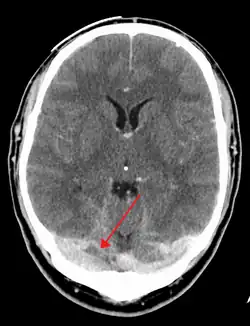

The diagnosis is usually by computed tomography (CT scan) or magnetic resonance imaging (MRI) to demonstrate obstruction of the venous sinuses.[3] After confirmation of the diagnosis, investigations may be performed to determine the underlying cause, especially if one is not readily apparent.

There are various neuroimaging investigations that may detect cerebral sinus thrombosis. Cerebral edema and venous infarction may be apparent on any modality, but for the detection of the thrombus itself, the most commonly used tests are computed tomography (CT) and magnetic resonance imaging (MRI), both using various types of radiocontrast to perform a venogram and visualise the veins around the brain.[3]

Computed tomography, with radiocontrast in the venous phase (CT venography or CTV), has a detection rate that in some regards exceeds that of MRI. The test involves injection into a vein (usually in the arm) of a radioopaque substance, and time is allowed for the bloodstream to carry it to the cerebral veins – at which point the scan is performed. It has a sensitivity of 75–100% (it detects 75–100% of all clots present), and a specificity of 81–100% (it would be incorrectly positive in 0–19%). In the first two weeks, the "empty delta sign" may be observed (in later stages, this sign may disappear).[11] The empty delta sign is characterized by enhancement of the dural wall without intra-sinus enhancement.[6]